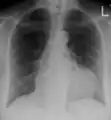

The diagnosis of tamponade can be confirmed with trans-thoracic echocardiography (TTE), which should show a large pericardial effusion and diastolic collapse of the right ventricle and right atrium. Chest X-ray usually shows an enlarged cardiac silhouette ("water bottle" appearance) and clear lungs. Pulmonary congestion is typically not seen because equalization of diastolic pressures constrains the pulmonary capillary wedge pressure to the intra-pericardial pressure (and all other diastolic pressures).

- A pericardial effusion as seen on CXR in someone with pericarditis